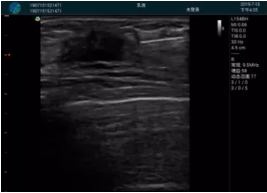

腺體內(nèi)部清晰顯示一低回聲塊影,形態(tài)不規(guī)則,邊界模糊,邊緣呈毛刺狀,內(nèi)部見砂礫樣鈣化